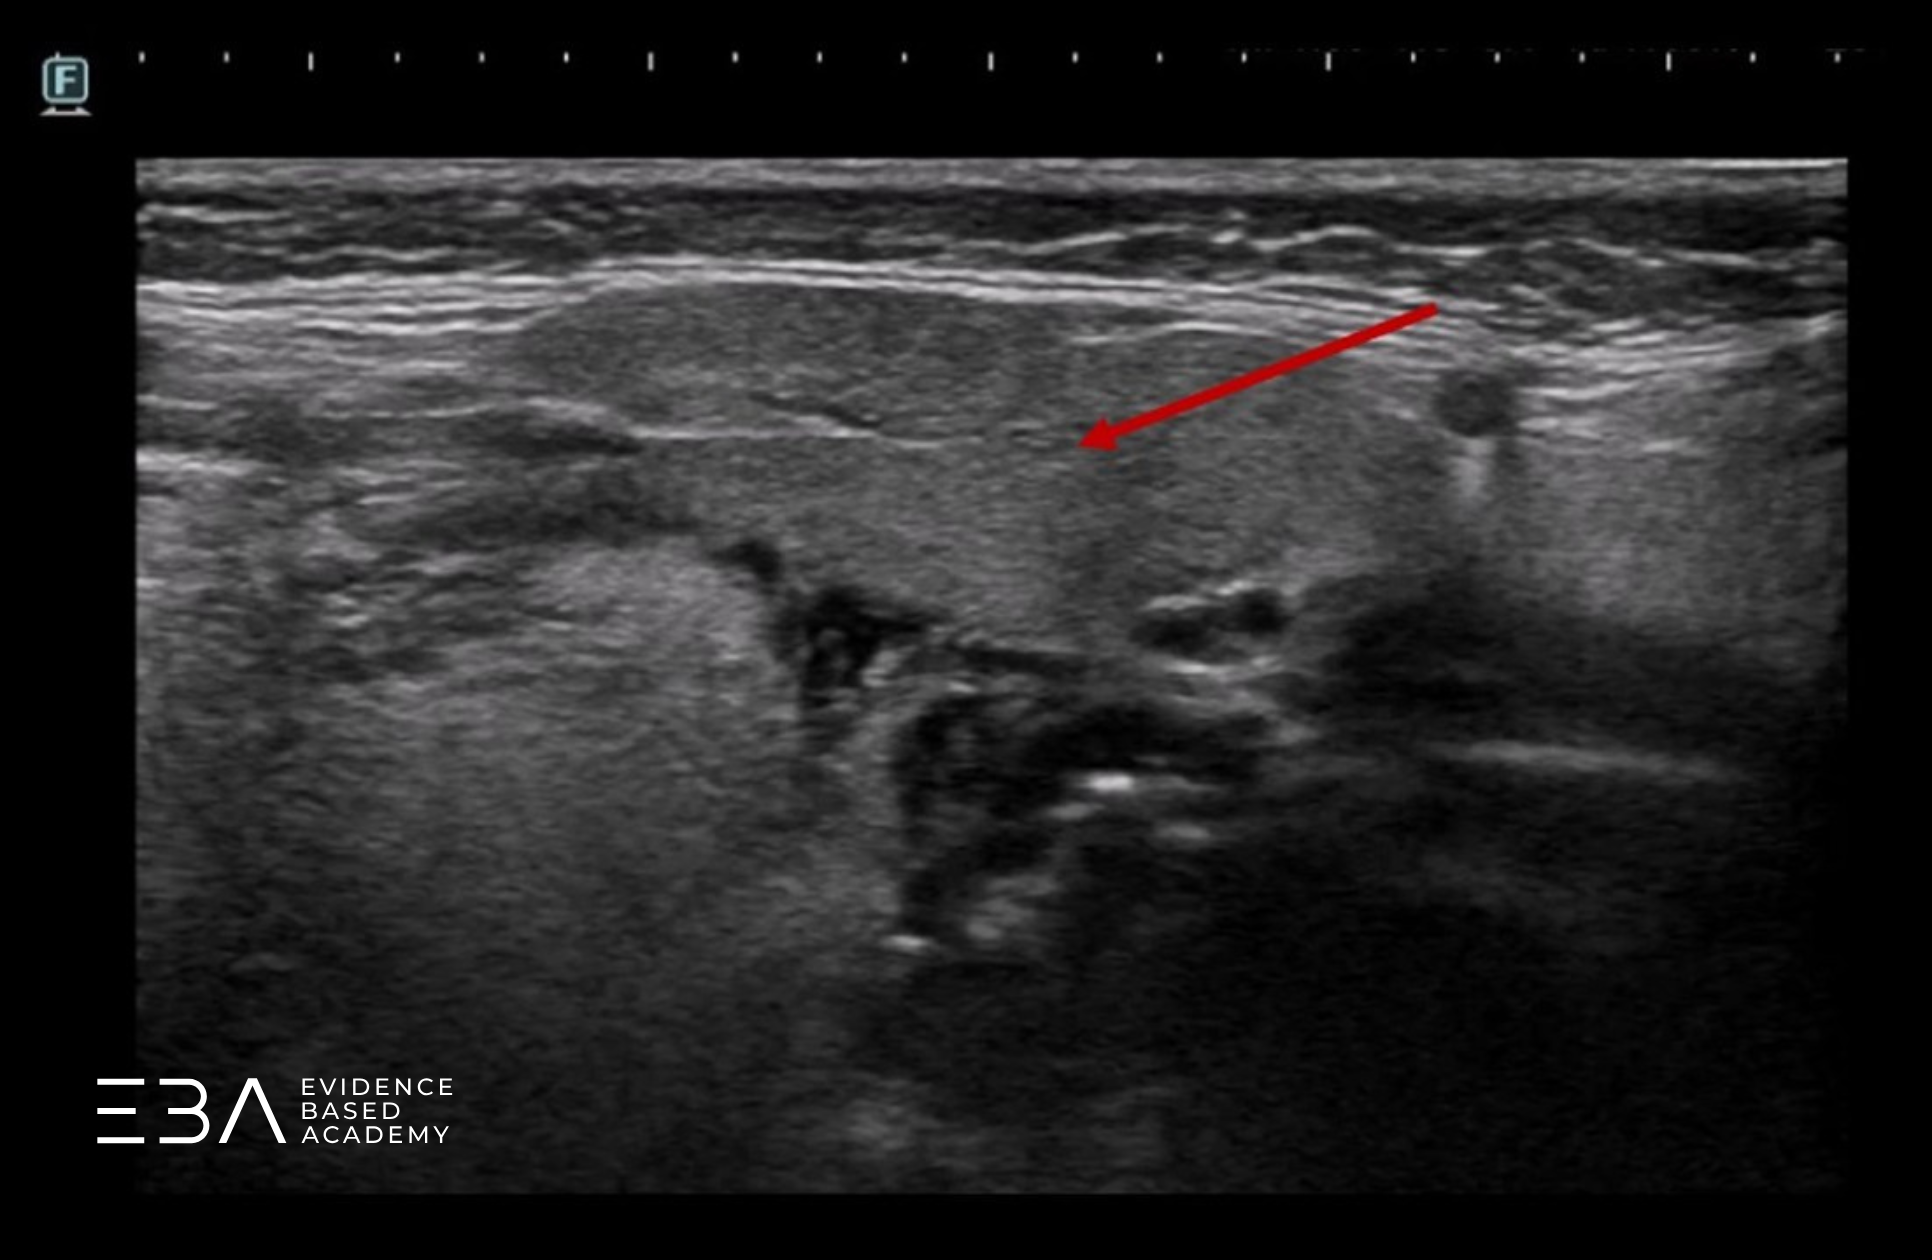

Torebka tarczycy w warunkach prawidłowych widoczna jest jako hiperechogeniczna, cienka linia oddzielająca miąższ tarczycy od struktur otaczających. Jej zarys jest gładki i regularny, możliwy do prześledzenia w każdej części tarczycy.

Torebka tarczycy.